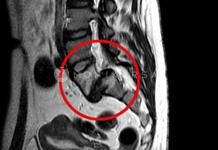

A hátfájás diagnózisa fizikai vizsgálattal és szükség esetén röntgen/CT/MR vizsgálattal történik.

A gerinc CT/MRI vizsgálatával a lágyrészek elváltozásai is kimutathatóak a hátfájásnál